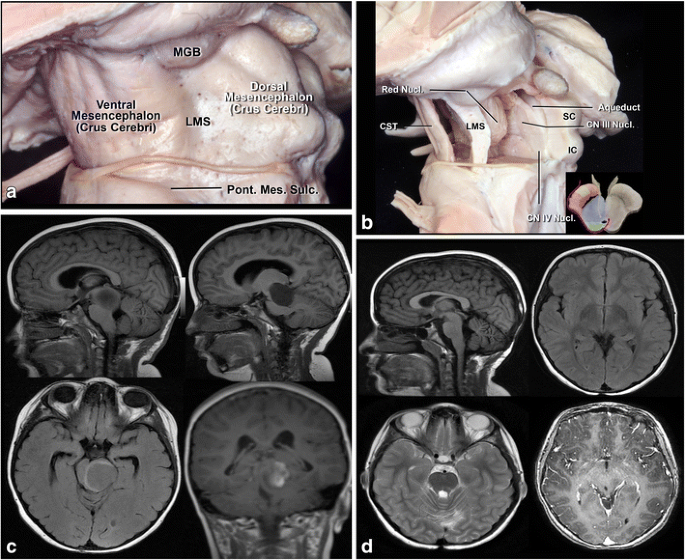

a Lateral view of the midbrain. The lateral mesencephalic sulcus (LMS) runs on the surface of the midbrain extending from the medial geniculate body (MGB) above to the pontomesencephalic sulcus (Pont. Mes. Sulc.) below. The LMS extends along the lateral edge of the medial lemniscus (ML). b The ML divides the midbrain into ventral (anterior) and dorsal (posterior) parts. Neurocritical structures at entry through the LMS are the corticospinal tract in the anterior midbrain, the red, oculomotor and trochlear nuclei in the central (tegmentum) midbrain, nuclei of the superior and inferior colliculus in the posterior (dorsal) midbrain. The oculomotor nucleus is positioned at the level of the inferior half of the superior colliculus and superior half of the inferior colliculus in the midline, and the trochlear nucleus is positioned at the level of the inferior half of the inferior colliculus in the midline. c Lateral lesion in the central midbrain approached via infratentorial supracerebellar route along the lateral sulcus of the mesencephalon. d Five-year follow-up after complete resection showing no evidence of the lesion, a pilocytic astrocytoma

a Schematic representation of the midbrain at the level of the oculomotor nerve. The substantia nigra and medial lemniscus is the border between ventral (anterior) and central parts of the midbrain, while the level of the cerebral aqueduct is the border between central (blue) and dorsal (posterior) midbrain (green). The corticospinal tract (yellow) in the ventral midbrain (red); nuclei and courses of the CN III (yellow) and IV (red) in the central (blue) and dorsal midbrain. b Lateral view of the midbrain. The ventral (anterior) midbrain, which contains the corticospinal tract (CST), is situated in front of the medial lemniscus (ML) and substantia nigra. The central midbrain containing the red, oculomotor and trochlear nuclei is positioned between medial lemniscus and aqueduct. The dorsal (posterior) midbrain composed of superior (SC) and inferior colliculi (IC) is positioned behind the cerebral aqueduct. The nuclei of the CN III and IV are located just ventral to the aqueduct. c Anterior view of midbrain. 1 Perioculomotor entry zone is bordered medially by exit point of the CN III and laterally by the corticospinal tract (CST). d The perioculomotor zone is limited by the posterior cerebral artery (PCA) superiorly and by the superior cerebellar artery (SCA) inferiorly

a. The brainstem surface anatomy. The brainstem is divided into three parts: the midbrain, pons, and medulla. The midbrain is limited superiorly by the sulcus between optic tract (OT) and crus cerebri, and inferiorly by the pontomesencephalic sulcus (Pon. Mes. Sulc.). The pons is positioned between the pontomesencephalic sulcus above and pontomedullary sulcus (Pont. Med. Sulc.) below. The medulla extends from the pontomedullary sulcus to the exit zone of the C1 nerve root. b, c , d The brainstem vascularization. The vertebral arteries (VA) meet to form the basilar artery at the level of the pontomedullary sulcus. The basilar artery (BA) gives rise to posterior cerebral arteries (PCA) at the level of the pontomesencephalic sulcus. The cerebellum has three surfaces: tentorial, petrosal, and suboccipital. The suboccipital surface of the cerebellum and medulla is supplied by the posteroinferior cerebellar artery (PICA). The petrosal surface of the cerebellum and pons are supplied by AICA and basilar artery perforators, while the midbrain and tentorial surface of the cerebellum is supplied by the superior cerebellar artery (SCA) branches. e Another division of the brainstem into seven compartments: the ventral, central, and dorsal midbrain; ventral and dorsal pons; and ventral and dorsal medulla. f Anatomical division of the brainstem according to course of the medial lemniscus (ML). In front of the ML can be considered the ventral brainstem, and behind the medial lemniscus as the dorsal brainstem

Midbrain